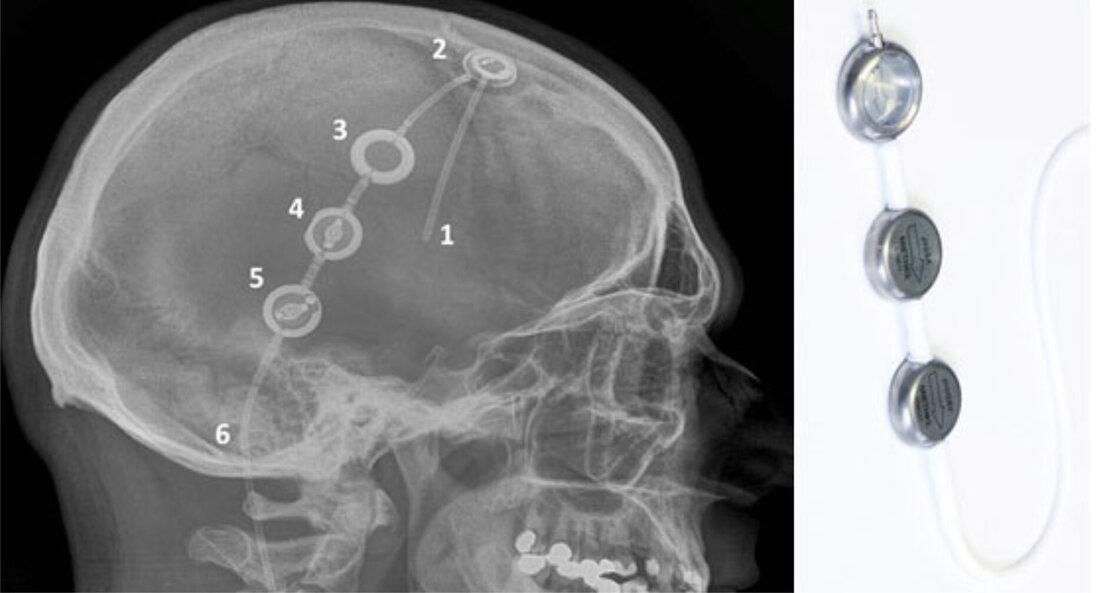

Im Bereich der Hydrocephalus-Therapie bietet unsere Klinik alle etablierten Verfahren an. Das häufigste Therapieverfahren im Rahmen eines Hydrocephalus ist die Implantation eines Shuntsystems zur Ableitung von überschüssigem Hirnwasser (Liquor). Hierbei wird über ein Schlauchsystem eine Verbindung zwischen den Hirnwasserkammern (Ventrikeln) und einer Körperhöhle – z. B. dem Bauchraum (Peritoneum) – geschaffen. Zur Regulation der Abflussmenge sind Ventile in das Shuntsystem zwischengeschaltet. Die von uns verwendeten Ventile können speziell auf den Patienten programmiert bzw. eingestellt werden. Das heißt, über eine Einstellung der sog. Ventil-Druckstufen wird vorgegeben, wie viel Hirnwasser nach der Operation aus dem Gehirn ablaufen soll.

Um das bestmögliche Therapieergebnis für den einzelnen Patienten zu erreichen, ist es zu jeder Zeit möglich, mit einem speziellen Magneten beliebig oft Umstellungen der Druckstufen über die geschlossene Kopfhaut vorzunehmen. Ein unbeabsichtigtes Verstellen mit normalen, handelsüblichen Magneten ist dabei nahezu ausgeschlossen. Durch die von uns etablierte Kombination von Langzeit-Hirndruckmessung (siehe oben) und Verwendung verstellbarer Ventile können insbesondere bei sehr schwierigen und komplexen Fällen hirndruckgesteuerte Ventileinstellungen zur Optimierung der Shunt-Therapie vorgenommen werden.